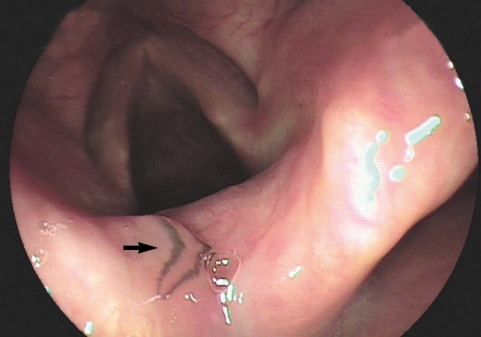

During a drug-induced sleep endoscopy for the upper airway and esophagus evaluation, a motile fluke was found attached to the surface of the arytenoid region (Fig. 1). The worm moving its posterior portion of the body peristaltically was immediately removed from the mucosa. It was partially torn at the lateral part of the middle one third when it was grasped by endoscopic forceps (Fig. 2). After removal of the worm, petechial hemorrhage was observed on the affected mucosa. The pain and other symptoms were gradually relieved. In unfixed condition, the fluke was 5.25 mm in length, 1.81 mm in maximum width at the posterior one third of the body. The oral sucker was located near the frontal end of the body. The ventral sucker was large and situated at the middle of the anterior one third of the body. The intestine of the worm was heavily dark due to ingested materials at its middle and posterior one third portion.